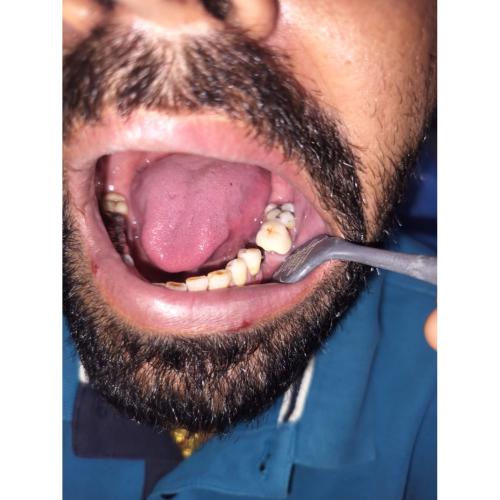

Single Implants

A single dental implant replaces one missing tooth with a titanium post and a custom crown. It preserves neighboring teeth (no need to file them for a bridge), protects jawbone health, and blends naturally for comfortable chewing and a seamless smile at Shree Jee Dental in Kishangarh. In select cases, a temporary tooth can be placed soon after surgery.

Multiple Implants

When several teeth are missing, multiple implants can support individual crowns or an implant-supported bridge. This approach avoids removable partial dentures, distributes bite forces evenly, and can restore longer gaps with fewer implants. Our Kishangarh team plans each case to balance function, aesthetics, and cost.

Single implants can be used to replaced one tooth broken or lost in an accident or disease.

Multiple implants

Have multiple missing teeth in a row? We might be able to replace them in a go